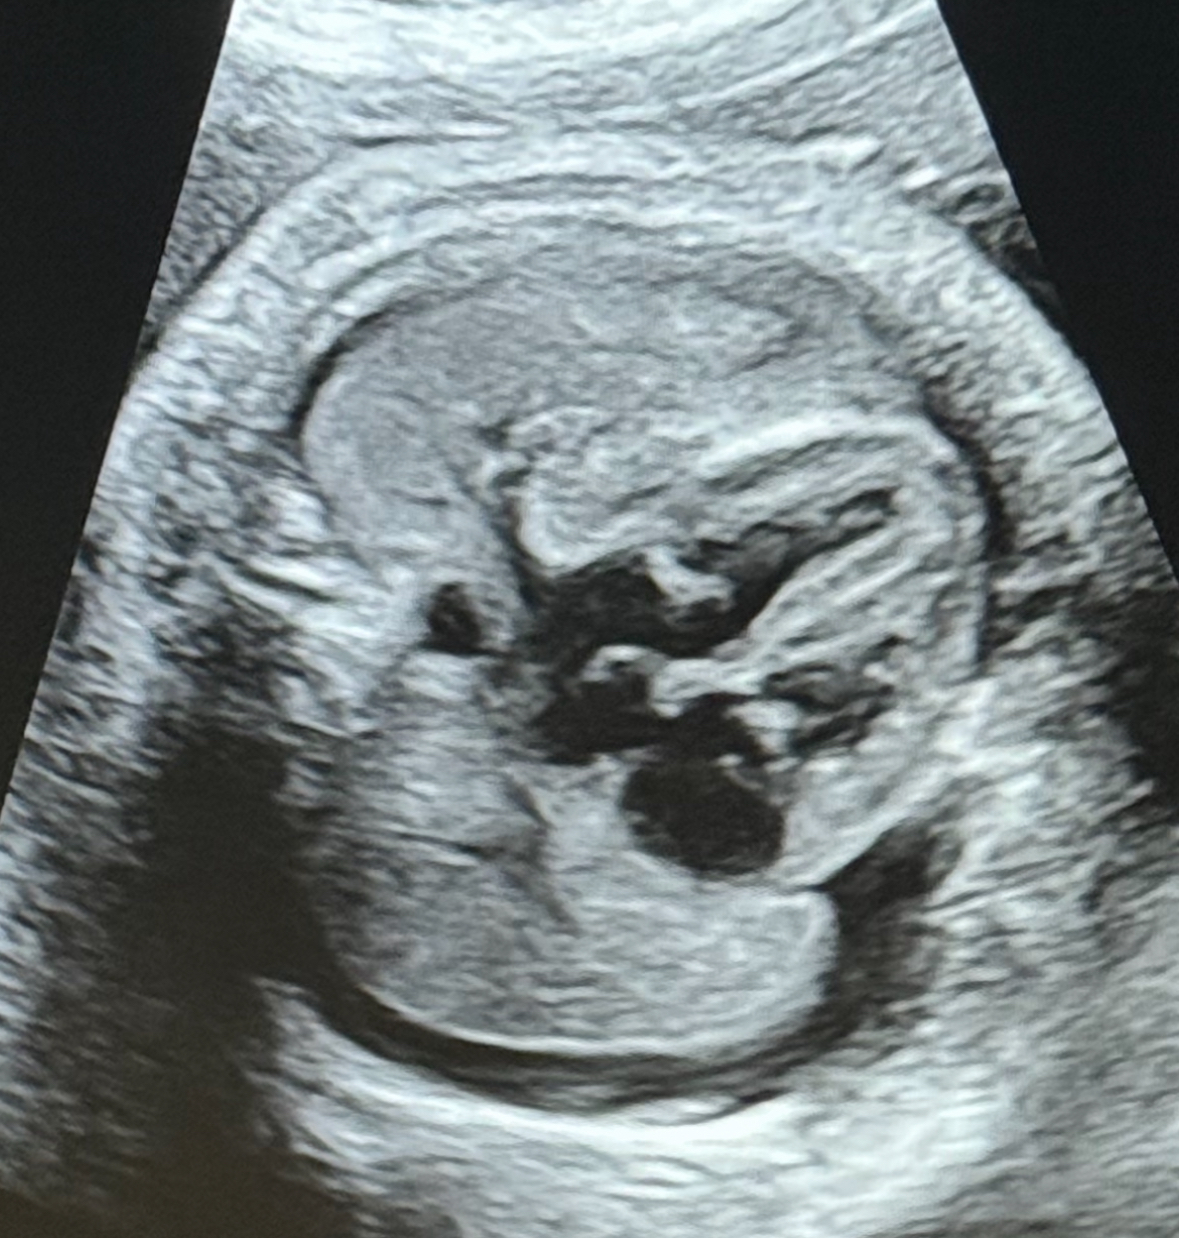

W ostatnich dniach w Klinice Położnictwa i Perinatologii Państwowego Instytutu Medycznego MSWiA w Warszawie wykonano kolejny zabieg z zakresu terapii płodu - po raz pierwszy w tej lokalizacji. U ciężarnej, będącej w 31 tygodniu ciąży, zdiagnozowano hydrothorax u płodu. Jest to nieprawidłowość, polegająca na obecności wolnego płynu w klatce piersiowej płodu, co uniemożliwia prawidłowy rozwój płuc i powoduje ich hypoplazję, jak również przemieszcza i uciska serce, prowadząc do niewydolności krążenia, która - w przypadku braku odpowiedniej terapii - może doprowadzić do śmierci płodu. Przyczyny takiego stanu mogą być natury genetycznej, infekcyjnej, endokrynologicznej, ale najczęściej pozostają nieznane - w takiej sytuacji rozpoznajemy postać idiopatyczną. Terapia hydrothorax polega na odbarczeniu płynu z klatki piersiowej płodu - można to uzyskać poprzez punkcję igłową, jednakże postępowanie takie jest mało efektywne, gdyż szybko dochodzi do nawrotu. Dlatego też metodą z wyboru jest założenie tzw. shuntu opłucnowo-owodniowego (cewnik typu double pig-tail), który umożliwia stały jednokierunkowy drenaż nadmiaru płynu.

Załączone zdjęcia pokazują zabieg (1), który wykonał zespół w składzie dr n. med. Michał Lipa i prof. dr hab. Mirosław Wielgoś oraz obrazy ultrasonograficzne, na których uwidoczniono sytuację wyjściową (2), założony shunt (3) i stan 4 dni po zabiegu (4). Doraźny efekt jest - jak widać na zdjęciach - bardzo dobry, w związku z czym Pacjentkę wypisano do domu. Z niecierpliwością oczekujemy na kontrolę, która odbędzie się w naszej Poradni Patologii Ciąży już za tydzień.